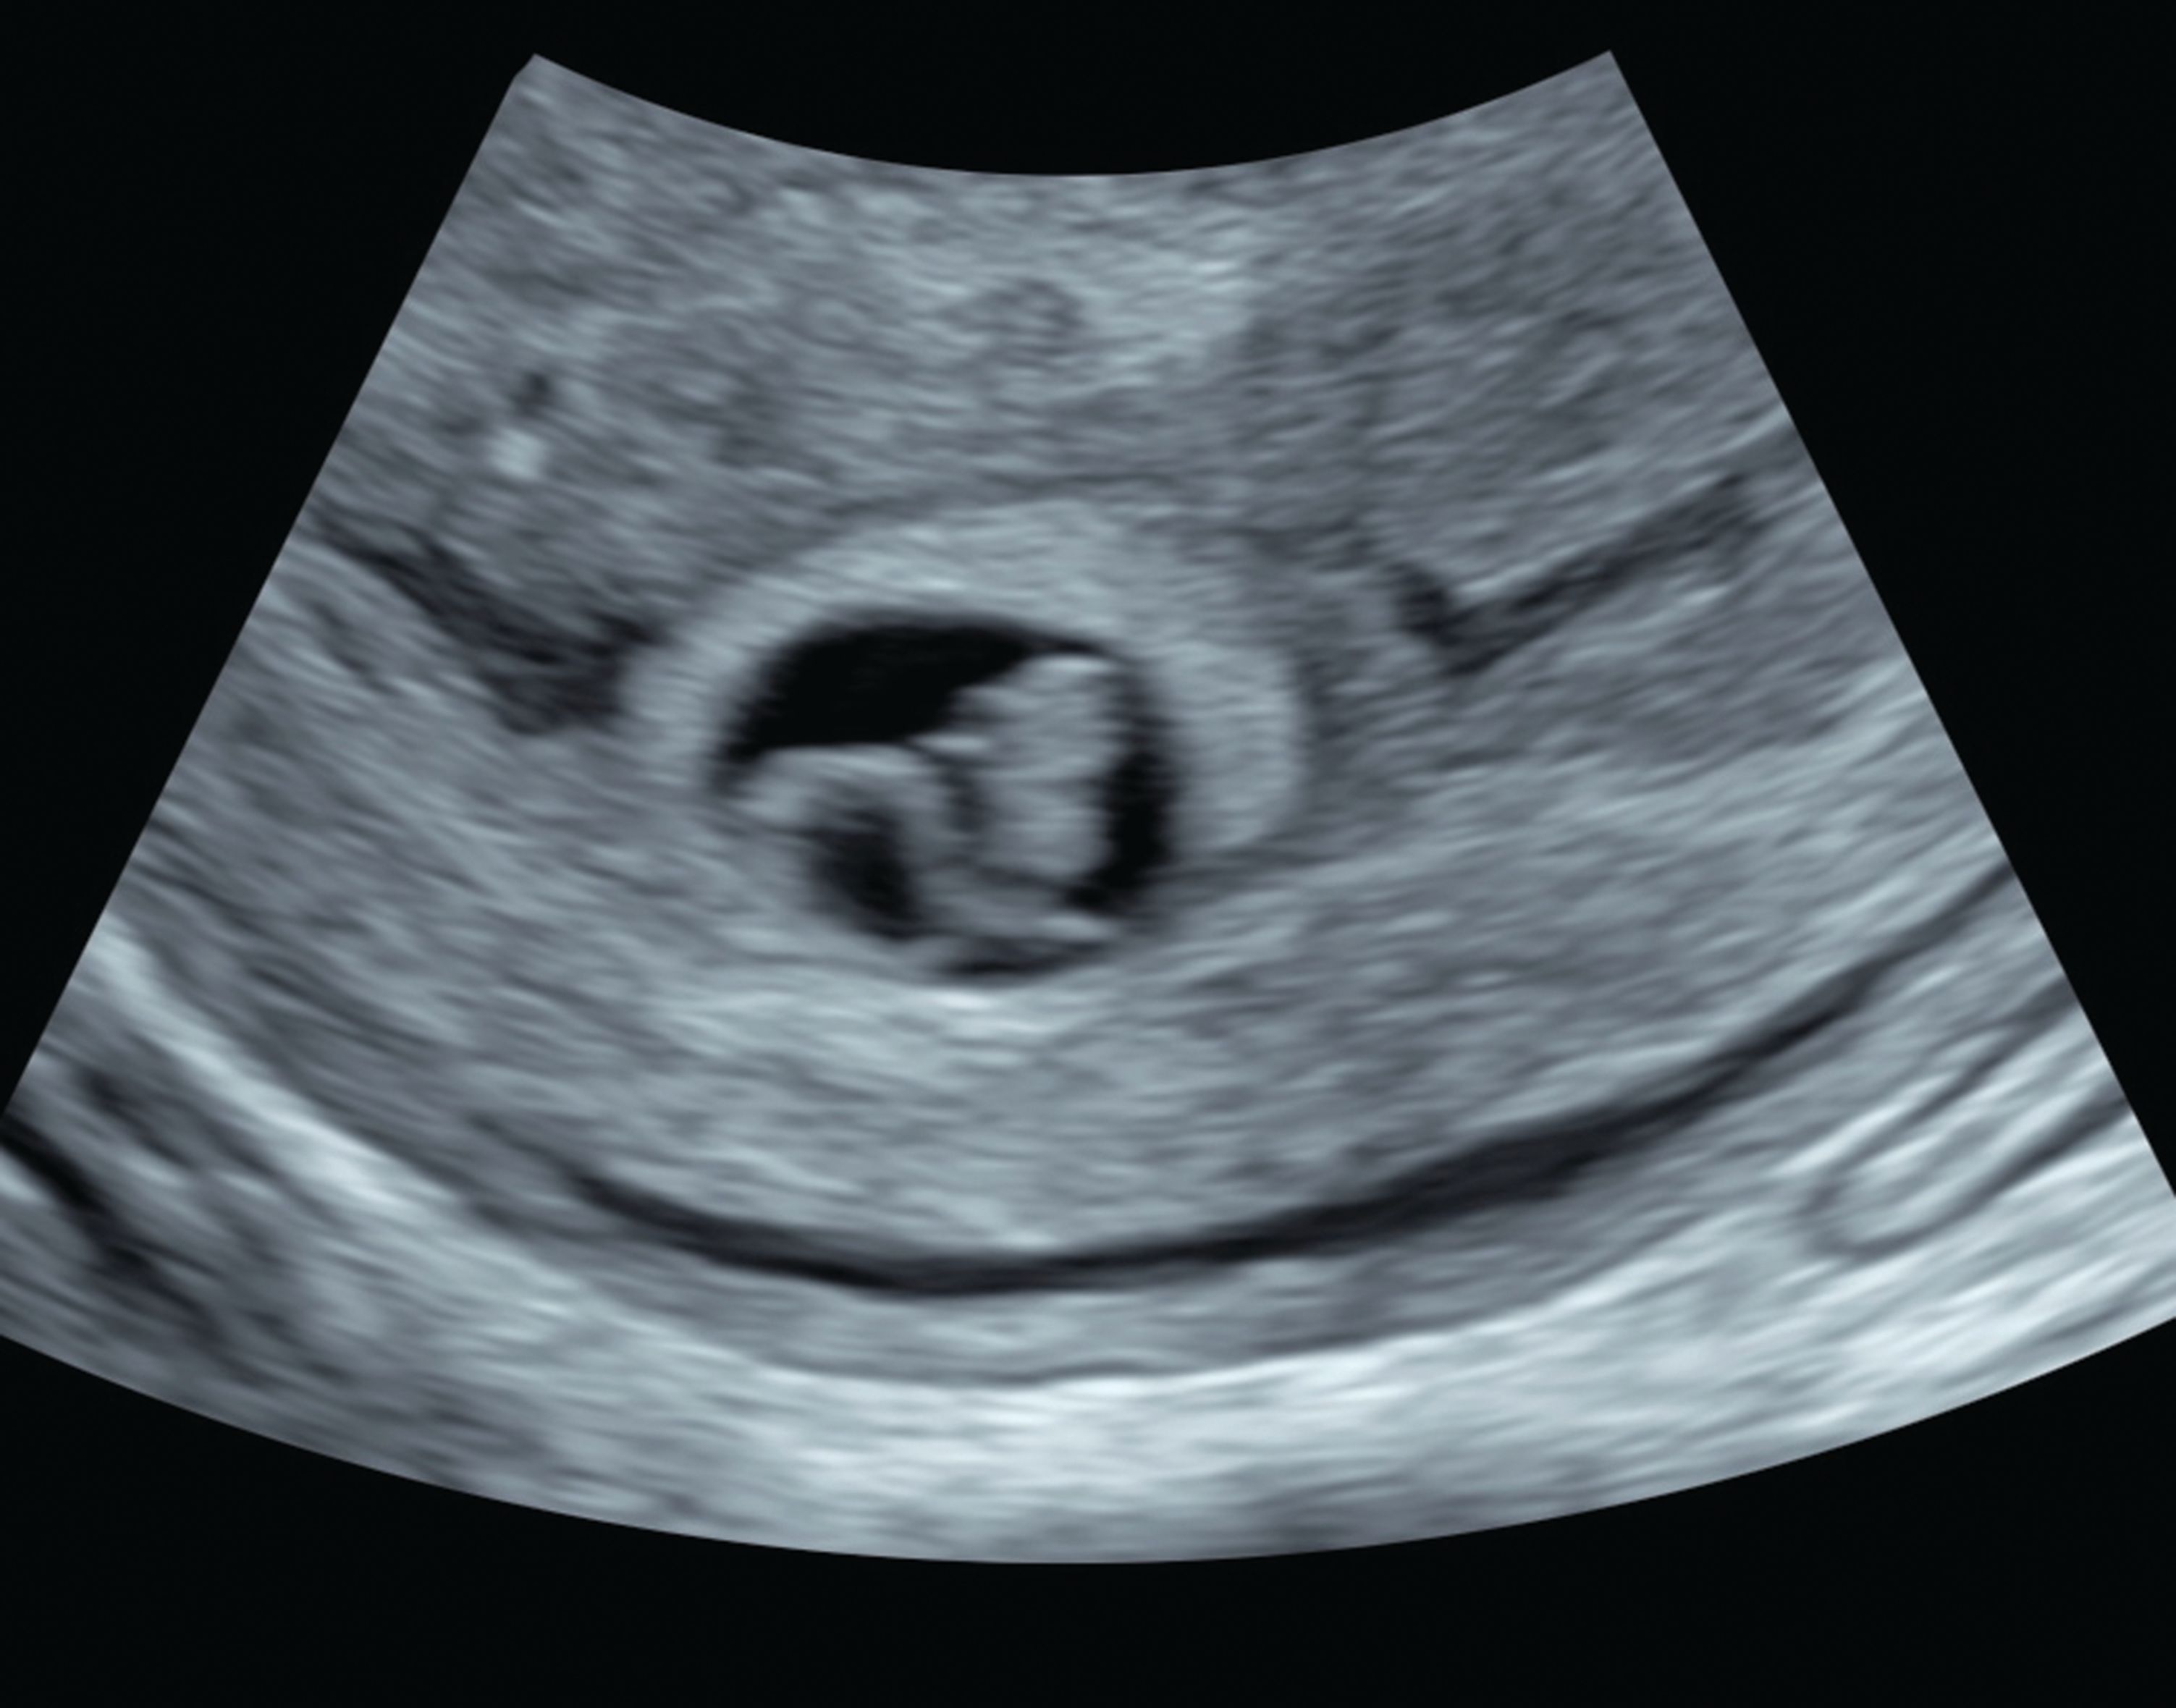

Will a miscarriage show on an ultrasound. Depending on where you are in your pregnancy the doctor can check your cervix monitor your hCG levels andor perform an ultrasound to determine whether you are miscarrying. An early ultrasound can show that fetal development or lack thereof was not viable before the actual onset of common symptoms such as bleeding and cramping. Approximately 20-25 of all pregnancies experience a threatened miscarriage.

Even in women with a confirmed miscarriage a pregnancy test may show a positive result for up to a month afterward. I thought I was 11w6d and at my OB appointment was told there is no heartbeat and baby stopped growing at 9w1d on an abdominal ultrasound. The subsequent ultrasound showing no signs of pregnancy usually would indicate a miscarriage.

A miscarriage often occurs very early in the pregnancy often without any alteration of the menstrual cycle and. Falling levels of hCG human chorionic gonadotropin a hormone thats made during pregnancy alongside an ultrasound that shows an empty gestational sac or no fetal heartbeat may also lead to a miscarriage diagnosis. This finding may be titled an early pregnancy failure Most miscarriages occur in the first trimester before the pregnancy has entered the 12th week.

There is a heartbeat or heartbeats if its a twin or multiple pregnancy and the pregnancy is the right size for dates that is the size that would be expected based on the first day of your last period. I plan on talking abou. Today the medical profession may use ultrasounds to identify the loss of a pregnancy.

Is that too soon. And Emilys sharing the heartbreaking story as a reminder to other women in similar situations that they are not alone. In addition if an earlier ultrasound revealed a fetal heartbeat and a subsequent ultrasound finds no heartbeat this also indicates a miscarriage.